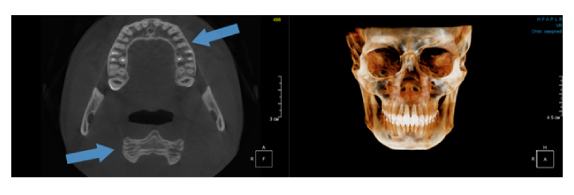

Рис. 2. Левый снимок представлен исследованием 20x20 см единым изображением. Стрелками показаны чёткость канально-корневой системы зуба, а также позвоночника. Правый снимок представлен исследованием 16x15 см с функцией сшивки. Стрелками обозначены чёткость зуба, но двойной контур позвоночника.